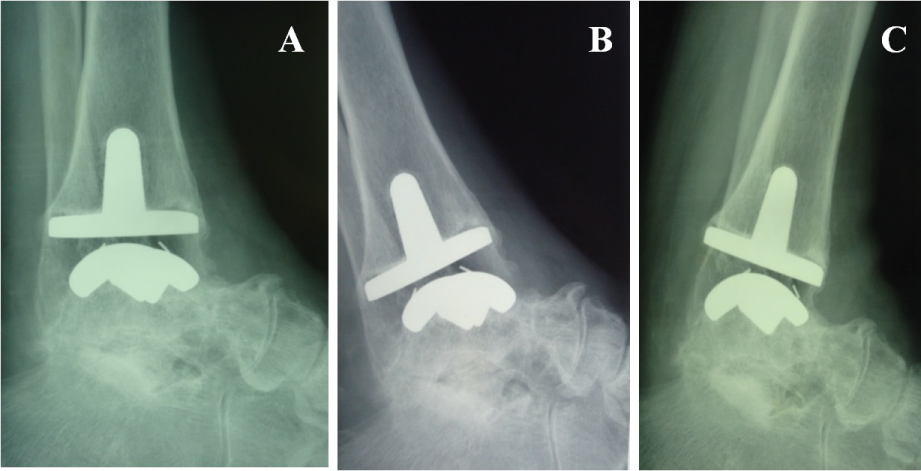

The radiographic assessment was based on antero-posterior (AP) and lateral weight bearing radiographs of the foot and ankle, as well as on lateral radiograph taken with the ankle in maximum plantar flexion and dorsiflexion. The Coetzee method allowed to determine the true ROM of the tibiotalar joint after total ankle arthroplasty [13] (Figure 3).

Figure 3: Radiographic lateral weight bearing assessment. A) Neutral position; B) Maximum plantar flexion; C) Maximum dorsiflexion. View Figure 3

The mean total range of ankle motion, assessed with the Coetzee method [14], improved from a mean of 21º ± 7.5º preoperatively (range 5º to 3º) to a mean of 31.7º ± 9.88º (range 10 to 50º) postoperatively at the 1-year follow-up, without statistical significance (p > 0.05).